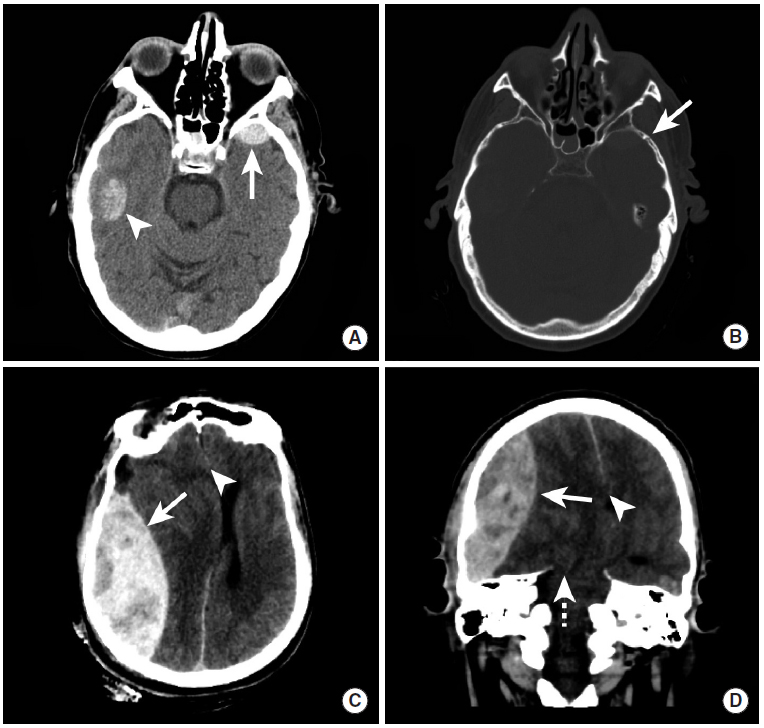

硬膜外血肿

图2

交通事故后创伤性硬膜下血肿两例。

图A、B:本例患者于意识状态低下时行影像学检查。右颞叶可见出血性脑实质挫伤(图A,三角箭头),同时左前颞叶前部可见半圆形硬膜外血肿灶(图A,长尾箭头)。骨窗影像可见硬膜外血肿附近存在非移位性颞骨骨折(图B,长尾箭头)。

图C、D:本例患者接受影像学检查时处于反应迟钝状态。平扫CT可见巨大的双凸面形硬膜外血肿(长尾箭头),并可见显著占位效应,导致左侧中线移位和大脑镰下疝(三角箭头),以及小脑幕切迹疝(虚线箭头)。